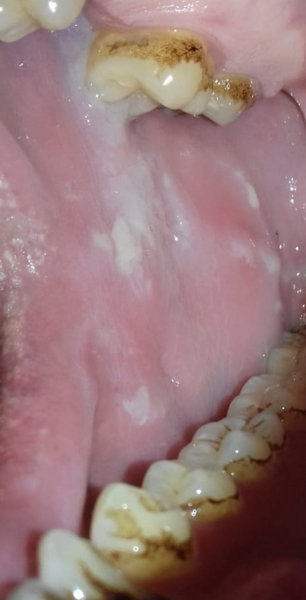

Недавно пришла цитология, где подтвердилась лейкоплакия твердого неба, вдобавок кандидоз полости рта. Пародонтолог прописал "Флуконазол" 5 дней по 50 мг, а пятно с лейкоплакией обрабатывать масляным раствором "витамина А" и "витамина Е" один раз в день на ночь, ротовые ванночки "Септомирин" в течение месяца.